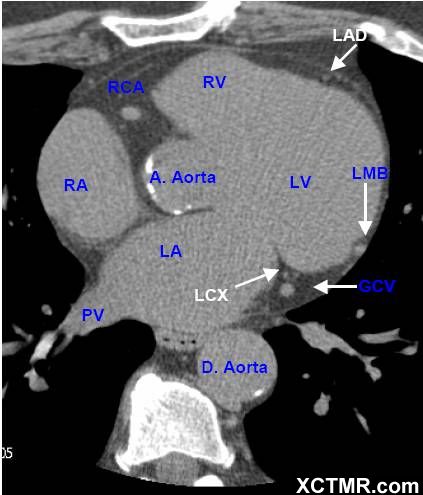

LA - Left Atrium 左心房

RA - Right Atrium 右心房

LV - Left Ventricle 左心室

RV - Right Ventricle 右心室

A. Aorta-Ascending Aorta 升主动脉

D. Aorta-Descending Aorta 降主动脉

PV - Pulmonary Vein 肺静脉

LAD - Left Anterior Descending Artery 左前降支

LCX - Left Circumflex Artery 左回旋支

LMB - Left Obtuse Marginal Branch 左边缘支(钝缘支)

RCA - Right Coronary Artery 右冠状动脉

GCV –Great Cardiac Vein 心大静脉